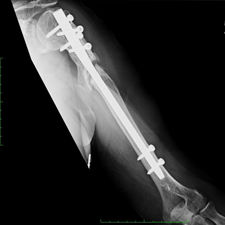

She was advised of the need to do some sort of stabilization which is necessary since the use of low-dose ultrasound has not helped in the healing process. She was unwilling to have any further operative intervention and sought further options. Eventually, she agreed to a fourth procedure of intra-medullary nail stabilization of the fracture and had this carried out in April 2011. An intramedullary nail was inserted in an antegrade manner and she has since gone on to heal the fracture site completely and has regained most of the function of the upper limb with no pain.

This case illustrates the possible complications that can occur with any surgery but also our commitment to our patients by sticking with them and making sure that a positive outcome is had despite the many challenges that may arise.